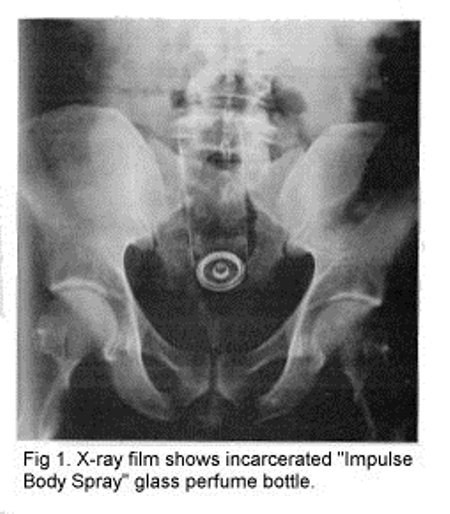

6. Um frasco de spray corporal